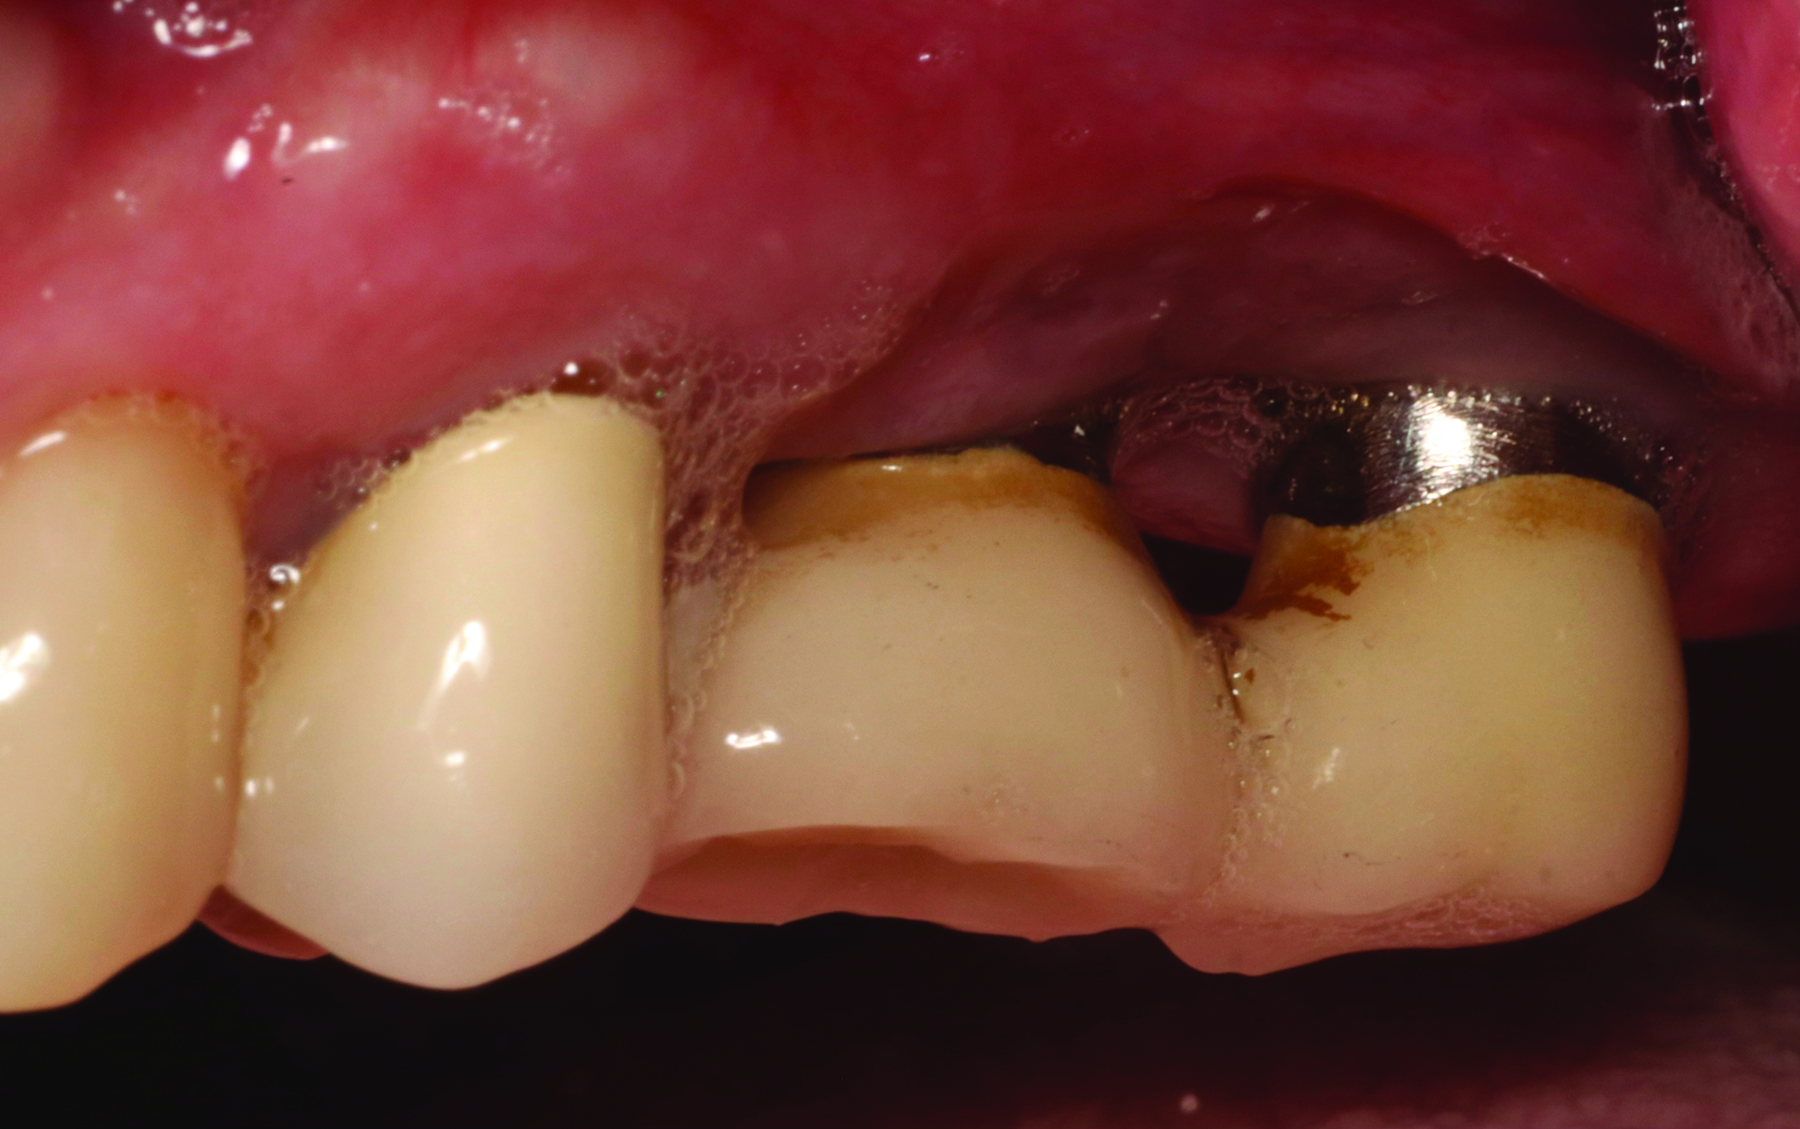

Fig 5 and Fig 6. Pre- (Fig 5) and post-treatment (Fig 6) photographs of a patient who received resective implant surgery to assess peri-implantitis at sites Nos. 14 and 15. Note the improved cleansability of the implants after surgery that opened the embrasure (Fig 6). The patient was placed on 3-month supportive peri-implant care post-surgery.

Figure 5

Figure 6